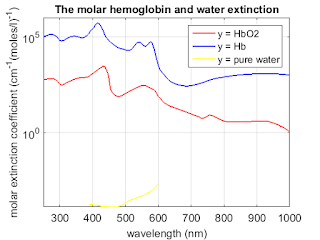

Matlab code to compute the corresponding absorption coefficients

% Matlab code to compute the corresponding absorption coefficients and plot

% the three absorption spectra on the same graph.

% Identify the low-absorption near-IR window that provide deep

% penetration.

% data for molar extinction coefficients of oxy-and deoxyhemoglobin and

% absorption coefficient of pure water as a function of wavelength are

% copied directly from this website: http://omlc.org/spectra/hemoglobin/summary.html

% Use physiologically representative values for both oxygen saturation SO2

% and total concentration of hemoglobin CHb.

% These values for the molar extinction coefficient e in [cm-1/(moles/liter)] were compiled by Scott Prahl using data from

%W. B. Gratzer, Med. Res. Council Labs, Holly Hill, London

%N. Kollias, Wellman Laboratories, Harvard Medical School, Boston

%To convert this data to absorbance A, multiply by the molar concentration and the pathlength. For example, if x is the number of grams per liter and a 1 cm cuvette is being used, then the absorbance is given by

%(e) [(1/cm)/(moles/liter)] (x) [g/liter] (1) [cm]

%A = ---------------------------------------------------

% 64,500 [g/mole]

%using 64,500 as the gram molecular weight of hemoglobin.

%To convert this data to absorption coefficient in (cm-1), multiply by the molar concentration and 2.303,

% µa = (2.303) e (x g/liter)/(64,500 g Hb/mole)

%where x is the number of grams per liter. A typical value of x for whole blood is x=150 g Hb/liter.

%% all three graph

figure;

semilogy(oxy_deoxy(:,1), oxy_deoxy(:,3)*0.0054, 'r', 'linewidth',1.5);

hold on

semilogy(oxy_deoxy(:,1), oxy_deoxy(:,2), 'b', 'linewidth',1.5);

hold on

semilogy(water(:,1), water(:,2), 'y', 'linewidth',1.5);

title('The molar hemoglobin and water extinction','FontSize',14);

set(gca,'FontSize',14);

ylabel('molar extinction coefficient (cm^{-1}(moles/l)^{-1})','fontsize',14);

xlabel('wavelength (nm)','fontsize',14);

%axis([250 1000 0 0.6*10^6]);

axis([250 1000 0 1*10^6]);

set(gcf,'PaperUnits','inches','PaperPosition',[0 0 6 5]);

grid on;

legend('y = HbO2 ','y = Hb', 'y = pure water')